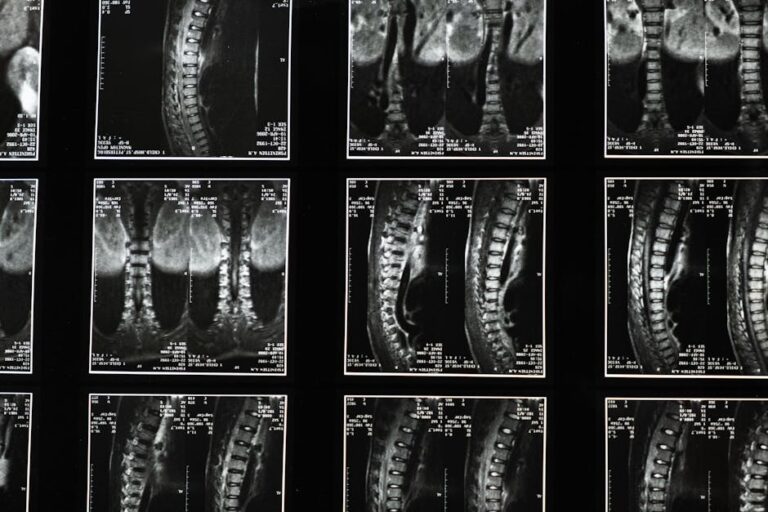

척추관 협착증은 척추관이 좁아져 신경을 압박하는 질환으로, 허리와 고관절 통증을 동시에 유발할 수 있어요. 주로 노화로 인한 퇴행성 변화가 원인이며, 엉덩이나 다리로 퍼지는 통증이 특징이죠.

허리디스크는 추간판이 탈출해 신경을 누르면서 허리와 고관절, 다리까지 통증이 퍼져요. 특히, 다리를 들어 올릴 때 전기가 흐르는 듯한 저림이 있다면 디스크를 의심해볼 필요가 있죠.